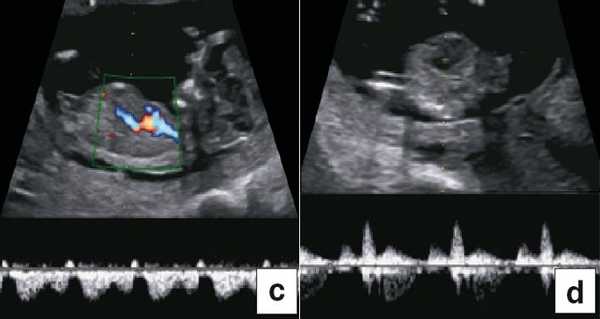

Тем не менее "базовое" УЗИ обычно дополняют исследованием в цветовом энергетическом допплеровском режиме с тщательным анализом для выявления атриовентрикулярного кровотока в четырех камерах сердца (рис. 6a) и в срезе через три сосуда и трахею (рис. 6b). Получив эти срезы, обычно можно успокоить родителей, исключив наличие тяжелых пороков сердца, таких как единственный желудочек, гипоплазия желудочков, полный дефект предсердно-желудочковой перегородки (atrioventricular septal defect - AVSD), атрезия аорты или легочной артерии, а также ряд аномалий расположения артерий.

Рис. 6. Эхокардиография плода на ранних сроках в цветовом энергетическом допплеровском режиме - визуализируются четыре камеры (a) и срез через три сосуда и трахею (b).